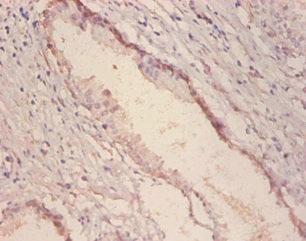

ApplicationELISA, IHC; Recommended dilution: IHC:1:20-1:200